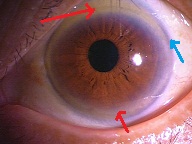

今日は水晶体亜脱臼による緑内障発作の患者様がいらっしゃり、お昼休みに緊急手術をさせて頂きました。

先日ハードレンズを処方した方の写真です。

先日ハードレンズを処方した方の写真です。